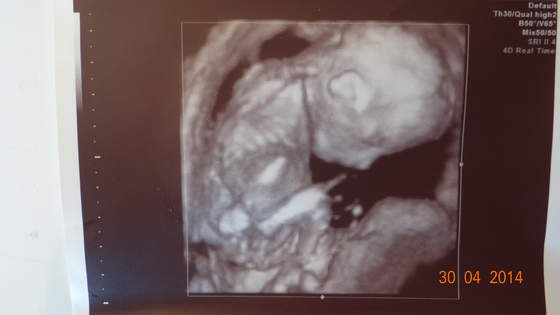

Jak to zazwyczaj bywa doktor powiadomil o badaniach prenatalnych - mam na mysli test podwojny z krwi + usg diadnostyczne (kosc nosowa i przeziernosc karkowa). W pierwszym tescie, usg bylo robione na wizycie kontrolnej i wyszlo ok a na tescie z krwi wyszlo prawdopodobienstwo zespolu downa 1:145 (dodam ze mam 23 lata!) telefon z przychodni.. szok.. Moj doktor postanowil ze powtorzymy badanie w szpitalu zeby skumulowac wyniki krwi i usg. I wyszlo juz lepiej chociaz i tak niezbyt niskie ryzyko bo 1:370. Wskazania do amnio sa od 1:300 ale pani genetyk stwierdzila ze wypisze skierowanie na wszelki wypadek i pozostawi do wlasnej decyzji chociaz zdecydowanych wskazan nie widzi.. tak jak wspomnialam nie zdecydowalismy sie na amniopunkcje. ale na usg plodu w 20-23 tc tak, aby przekonac sie w 100% ze nasz synek jest zdrowy

nie ma widocznych wad serca wiec wykluczamy tez ZD przy ktorym jak wiadomo czesto wystepuja wady wrodzone, nosek tez ma pieknie widoczny, duzy.. smieje sie ze po tatusiu

Synus jest bardzo ruchliwy i buntowniczy na badaniu pani doktor az sie na niego zdenerwowala